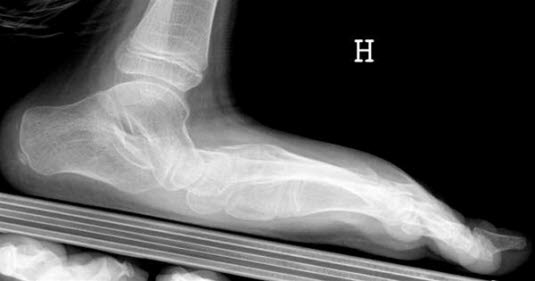

Foten er buet i to retninger, i lengderetningen og tvers over forfoten. Plattfot innebærer at fotbuene er reduserte eller mangler helt. Det skilles mellom en myk type, der det er normal fotbue når pasienten står på tær, og en stiv type der foten er flat hele tiden. Stiv plattfot kan i noen tilfeller gi plager.

Plattfot påvises ved undersøkelse av føttene. Den indre fotbuen siger ned mot underlaget når foten belastes. Ved den vanlige myke plattfot får foten normal fasong når trykket avlastes, som for eksempel når man står eller går på tærne. Dette i motsetning til stiv plattfot der foten alltid er flat, for eksempel på grunn av sammenvoksninger mellom ben i foten.

Røntgenundersøkelser er ikke nødvendig ved plattfot annet enn i de tilfellene hvor det foreligger stiv plattfot og pasienten plages med smerter.

Stiv plattfot fører ofte til plager ved økende alder og økende aktivitet. Spesialtilpassede såler (myke fotsenger) kan være aktuelt ved stiv plattfot. Ved vedvarende plager kan utredning med CT og/eller MR være aktuelt. Ved skjelettskader eller nerve og muskelsykdom kan operasjon i foten være aktuelt.